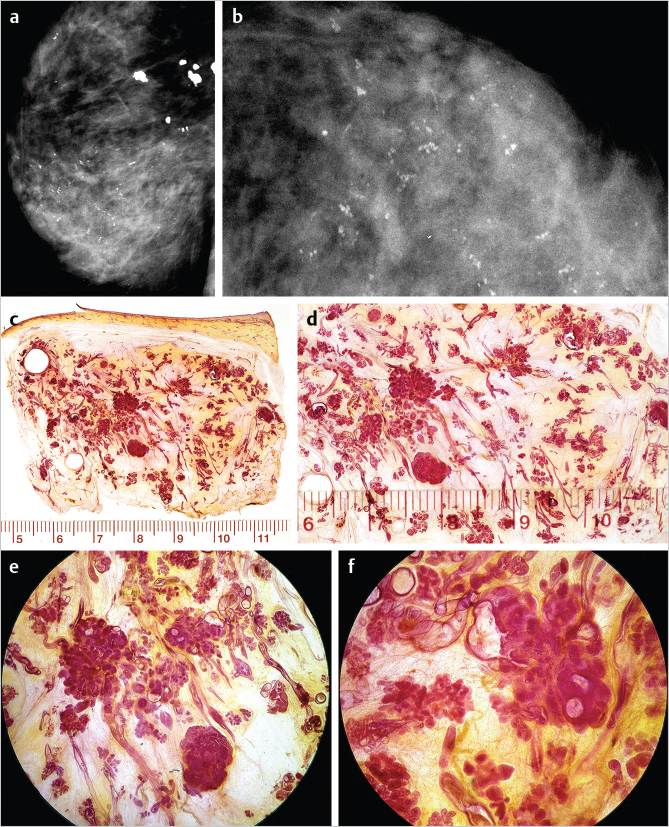

The examples on ▶Fig. 6.4 and ▶Fig. 6.5 represent multifocal grade 2 and grade 1 in situ AABs. The distribution of the calcifications in both grades 1 and 2 appears as multiple clusters on the mammograms, because the malignant process is confined to the TDLUs. The mammographic images shown on ▶Fig. 6.4 and ▶Fig. 6.5 clearly reflect the differences in the respective underlying histopathology: in grade 2 in situ AAB, the calcifications are the result of tumor necrosis within the TDLUs (▶Fig. 6.4), and are seen on the mammogram as multiple cluster, discernable, crushed stone-like microcalcifications. On the other hand, in grade 1 in situ AAB, the cancer cells produce fluid within which psammoma body-like calcifications are formed, seen as powdery calcifications on the mammogram (▶Fig. 6.5).

Example: Multifocal Grade 2 AAB

This 86-year-old woman was referred to mammography for a palpable thickening in her right breast (▶Fig. 6.4).

Multiple clusters of crushed stone-like/pleomorphic calcifications on the mammogram. ▶Fig. 6.4 is an example a multifocal grade 2 in situ AAB, indicated by the presence of multiple clusters of crushed stone-like calcifications on the mammogram.